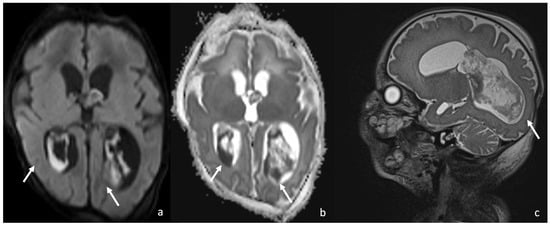

- Late cerebritis (5–14 days): Cerebritis progressively evolves to show a necrotic core and an initial encapsulation. This stage flows into and partly overlaps with the early capsule stage since this last represents a progression with similar, yet more advanced features of the late cerebritis stage. In MRI, the late cerebritis results in a focal formation characterized by a necrotic core, appearing inhomogeneous on both T1 and T2WI, without a complete and regular contrast peripheral enhancement, yet with a defined diffusion restriction on DWI/ADC. On the US, the appearance is similar to the early cerebritis, yet the lesion appears more focal and the core starts becoming hypoechogenic, similar to CT showing a significantly hypodense core in the lesion with irregular and incomplete peripheral enhancement. Early capsule formation (14–30 days): The cerebritis is becoming an abscess since the capsule is evident, yet it is incomplete and thin and appears as a hyperintense rim on T1WI and a hypointense rim on T2WI with contrast enhancement on T1WI.

- Early capsule formation (2 weeks to 2 months): the lesion presents diffusion restriction on DWI/ADC, mainly in relation to hypercellularity. Sonographically, the lesion presents a well-defined hypoechoic core and an incomplete hyperechoic rim. CT shows a well-defined hypodense core and an incomplete peripheral enhancement.

- Late capsule formation (weeks to months): The parenchymal abscess presents a necrotic core, appearing hypointense on T1WI and hyperintense on T2WI with diffusion restriction on DWI/ADC. The capsule is inhomogeneously thick, appearing thicker towards the cortex and thinner towards the ventricles, appears isointense on T1WI and hypointense on T2WI, and presents an intense enhancement. On the US, the abscess presents a well-defined hypoechoic core and a complete hyperechoic rim, pairing CT that shows a well-defined hypodense core and a complete peripheral enhancement.